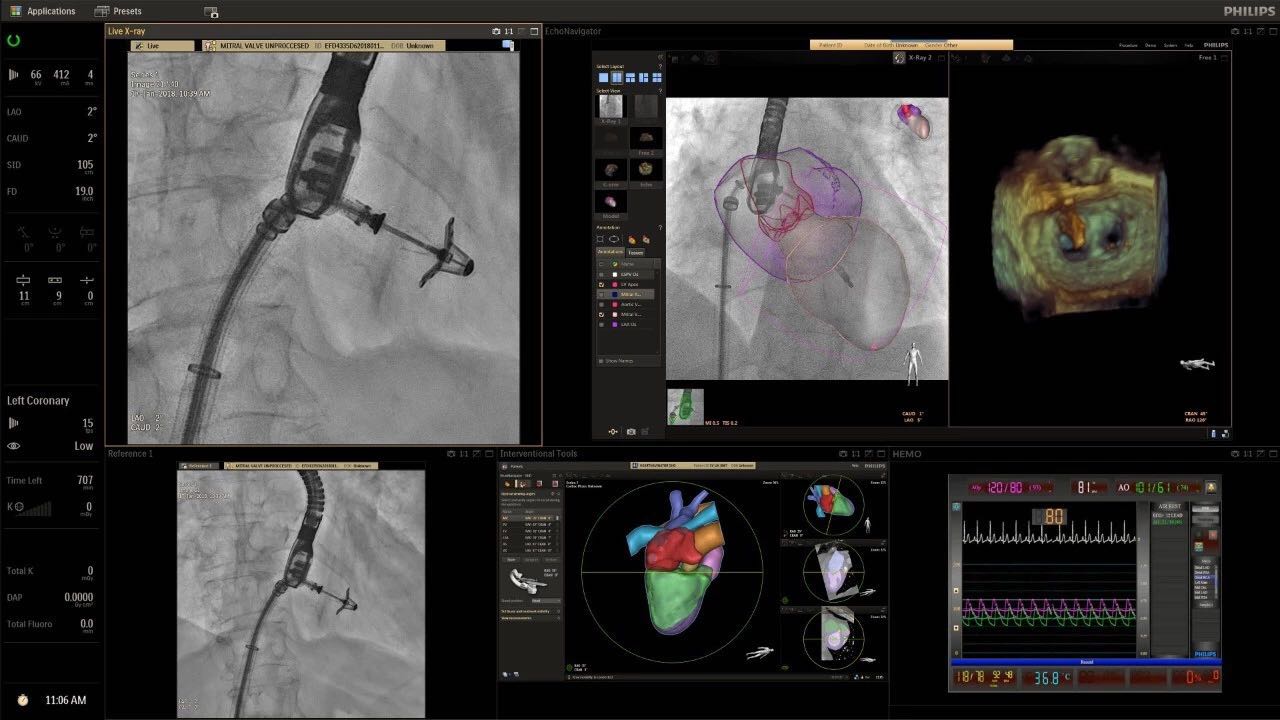

在日益復(fù)雜的干預(yù)期間,臨床醫(yī)生需要快速、輕松地可視化關(guān)鍵解剖結(jié)構(gòu)并確定手術(shù)過(guò)程中患者的變化。2019年1月17日,飛利浦宣布推出采用FlexArm的Azurion 7 C20,旨在提高圖像引導(dǎo)程序的定位靈活性。

帶有FlexArm的Azurion 7 C20 包含一系列創(chuàng)新技術(shù),使臨床醫(yī)生可以更輕松地在整個(gè)患者身上進(jìn)行二維和三維成像。當(dāng)臨床醫(yī)生移動(dòng)系統(tǒng)時(shí),圖像光束自動(dòng)保持與患者的對(duì)準(zhǔn),允許更一致的可視化并使他們能夠?qū)⒆⒁饬性谥委熒稀?/span>

“憑借FlexArm,飛利浦的工程師已經(jīng)克服了幾乎不可能的幾何和機(jī)械障礙,使臨床醫(yī)生能夠在圖像引導(dǎo)治療方面實(shí)現(xiàn)臨床卓越,”邁阿密心臟與血管研究所創(chuàng)始人兼首席醫(yī)療主管Barry T. Katzen博士說(shuō)?!癋lexArm使我們能夠大大優(yōu)化患者周圍的程序,我們可以最佳地了解患者體內(nèi)的情況,而不會(huì)妨礙所有在桌面上工作的臨床醫(yī)生。結(jié)果是一項(xiàng)不僅具有臨床重要性,而且使用起來(lái)非常簡(jiǎn)單直觀的創(chuàng)新。這是復(fù)雜手術(shù)過(guò)程中的一個(gè)關(guān)鍵因素?!?

(FlexArm C型臂可以沿著工作臺(tái)的兩側(cè)提供偏心成像。這允許醫(yī)生在左臂或右臂上進(jìn)行徑向進(jìn)入病例,完全或部分伸展,而無(wú)需移動(dòng)患者或樞轉(zhuǎn)桌子。X射線束與手臂保持對(duì)齊,以促進(jìn)其整個(gè)長(zhǎng)度的平滑導(dǎo)航,而無(wú)需進(jìn)行持續(xù)調(diào)整。)

飛利浦表示,采用FlexArm設(shè)計(jì)的Azurion 7 C20可提供卓越的靈活性和直觀的控制。該系統(tǒng)由智能運(yùn)動(dòng)引擎驅(qū)動(dòng),可在八個(gè)不同的軸上移動(dòng),所有這些軸均由其單個(gè)“Axsys”控制器控制。臨床醫(yī)生的模擬測(cè)試表明,該系統(tǒng)有可能顯著減少患者,工作人員和設(shè)備的重新定位,從而改善微創(chuàng)手術(shù)的可及性,包括通過(guò)患者手腕進(jìn)入身體的手術(shù)(橈動(dòng)脈入路),并降低患者的風(fēng)險(xiǎn)。無(wú)意中拔出電線和管子,以及節(jié)省大量時(shí)間。該系統(tǒng)非常適合混合手術(shù)室(OR),可滿足一個(gè)房間內(nèi)的多種專業(yè)需求,例如手術(shù)和血管內(nèi)手術(shù)的組合。

FlexArm在不少于8軸的情況下旋轉(zhuǎn),從而創(chuàng)建幾乎無(wú)限的靈活性來(lái)執(zhí)行成像,從頭部到腳部在左側(cè)和右側(cè)進(jìn)行2D和3D可視化。圖像光束保持與患者對(duì)齊,允許在旋轉(zhuǎn)或角度期間更好地可視化解剖結(jié)構(gòu)。使用Axsys運(yùn)動(dòng)控制系統(tǒng)輕松操作支架。